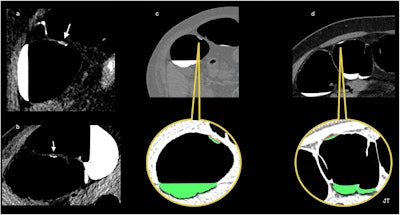

Flat-serrated lesions. This true flat polyp appears as a < 3-mm-high nonpolypoid tissue lesion spreading on the surface at a fixed location on a right lateral decubitus and (b) left decubitus positioning, and covered by a thin film of oral contrast, demonstrating the floating oral contrast-coating sign. (c) The surface of the oral-contrast sign in contact with the polyp is depicted as an undulating red line. The green is an artifice to color liquid in the colon to improve visualization. (d) The stool adhering to the colon wall in another patient appears as the contrast-agent sign in contact with the wall and is seen as a smooth and regular surface with a concave appearance (red line).